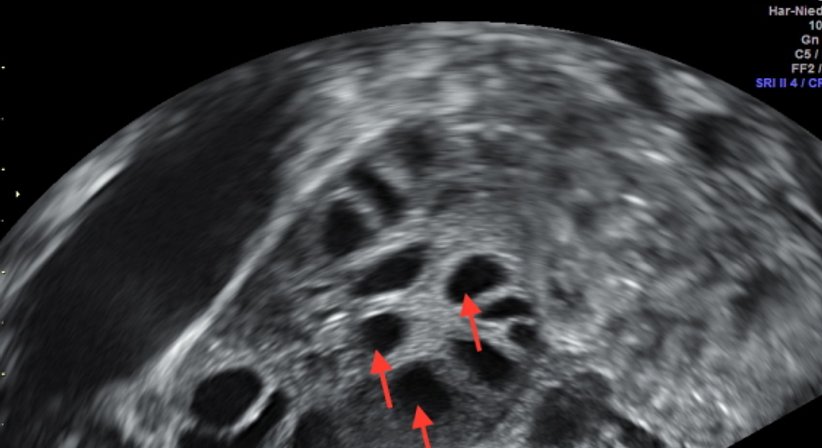

2. AFC, Antral Follikel Count – Bestimmung der Zahl der Follikel per Ultraschall während der Menses)

• HyCoSy – Tubendurchgängigkeitsprüfung ohne Strahlenbelastung mit 3D-Ultraschall.